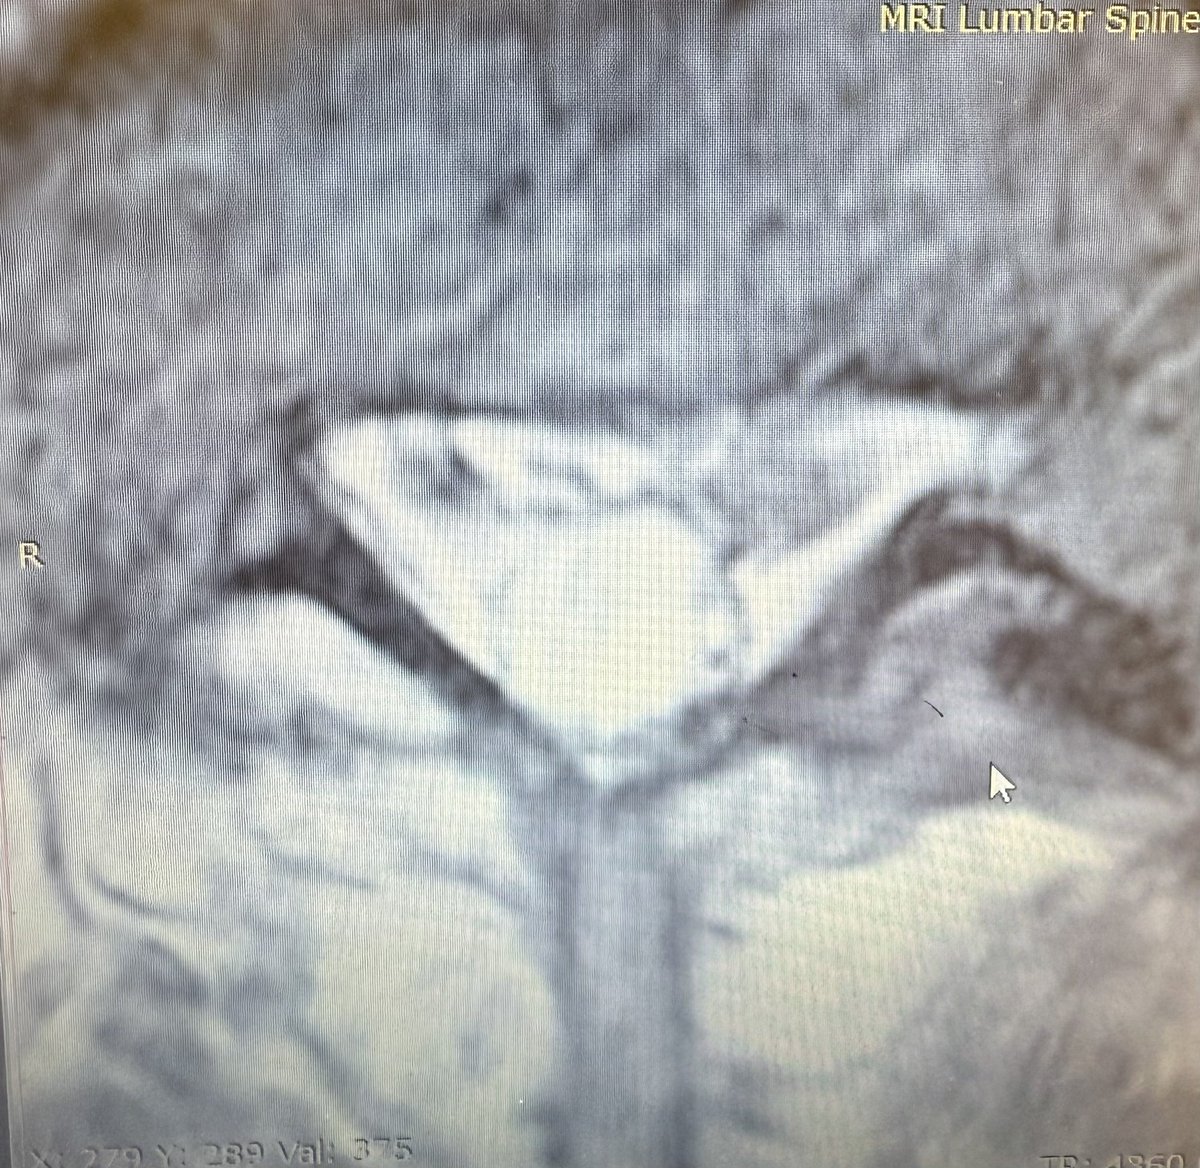

Clumping of the nerve roots in arachnoiditis is very commonly missed even in patients like this with chronic leg pain after trauma and prior surgery. keep an eye out for abnormal distribution and clumping of nerve roots in the cauda equina.